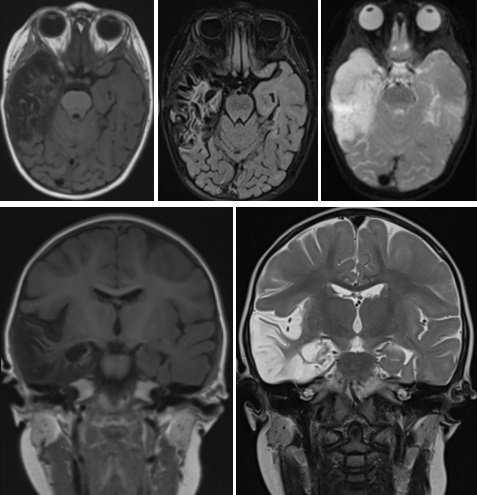

Tras los resultados microbiológicos de la punción lumbar, detectándose en LCR una reacción en cadena de la polimerasa (PCR) positiva para VHS tipo 1, se mantiene tratamiento con aciclovir intravenoso durante 21 días. A los 18 días de ingreso se realiza una resonancia magnética (RM) cerebral en la que se observan secuelas de encefalitis herpética con marcada pérdida de volumen del lóbulo temporal e hipocampo derechos con dilatación compensadora del ventrículo lateral. Así mismo se aprecia sutil pérdida de volumen con prominencia de espacios de LCR a nivel del hipocampo y giro parahipocampal izquierdos (Fig. 2).

| Figura 2. Resonancia magnética craneal. Cortes axiales y coronales. Secuelas de encefalitis herpética con importante destrucción fundamentalmente del lóbulo temporal e hipocampo derechos y de forma muy sutil hipocampo y giro parahipocampal izquierdos |